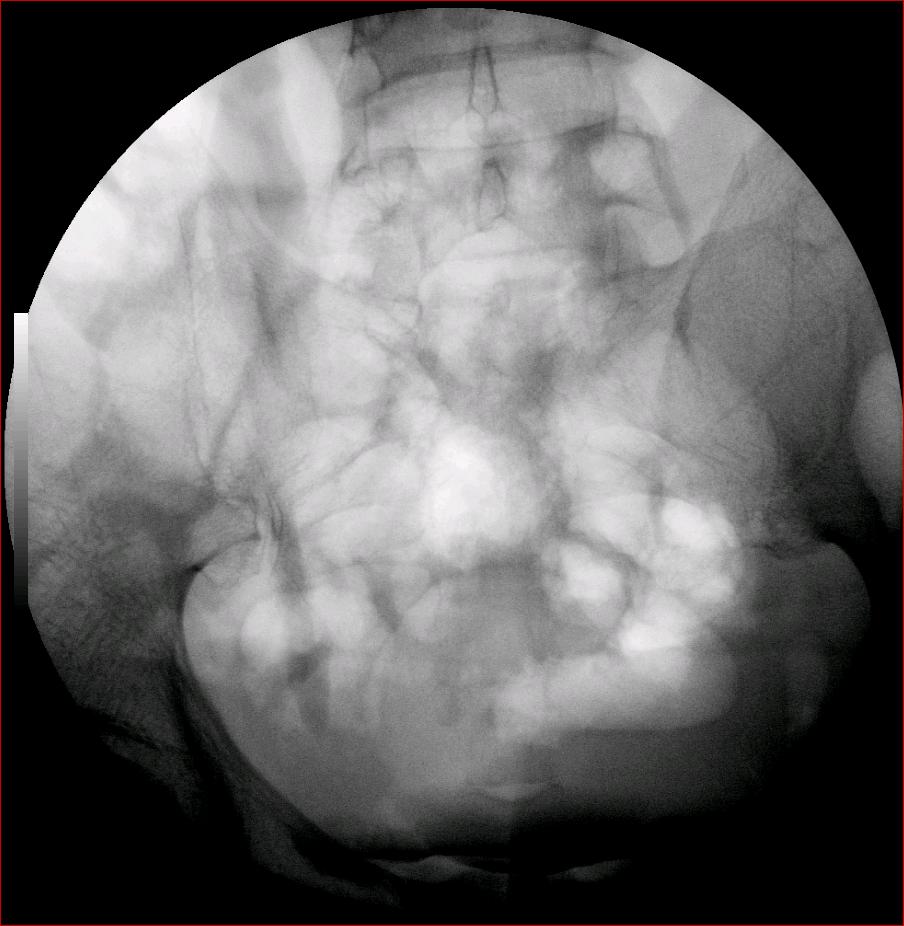

以下是引用luoxinjun在2008-2-18 15:54:00的发言:[br]右肾积水,右输尿管下端结石

以下是引用zhangxiangjun在2008-2-18 21:01:00的发言:[br]右输尿管盆段末端结石,继发其近端输尿管、右肾积水。

以下是引用hexue在2008-2-18 17:33:00的发言:[br]右输尿管下段结石并右肾及右输尿管积水扩张

以下是引用杀毒软件在2008-2-18 16:24:00的发言:[br]右输尿管下段结石,肾盂积水。